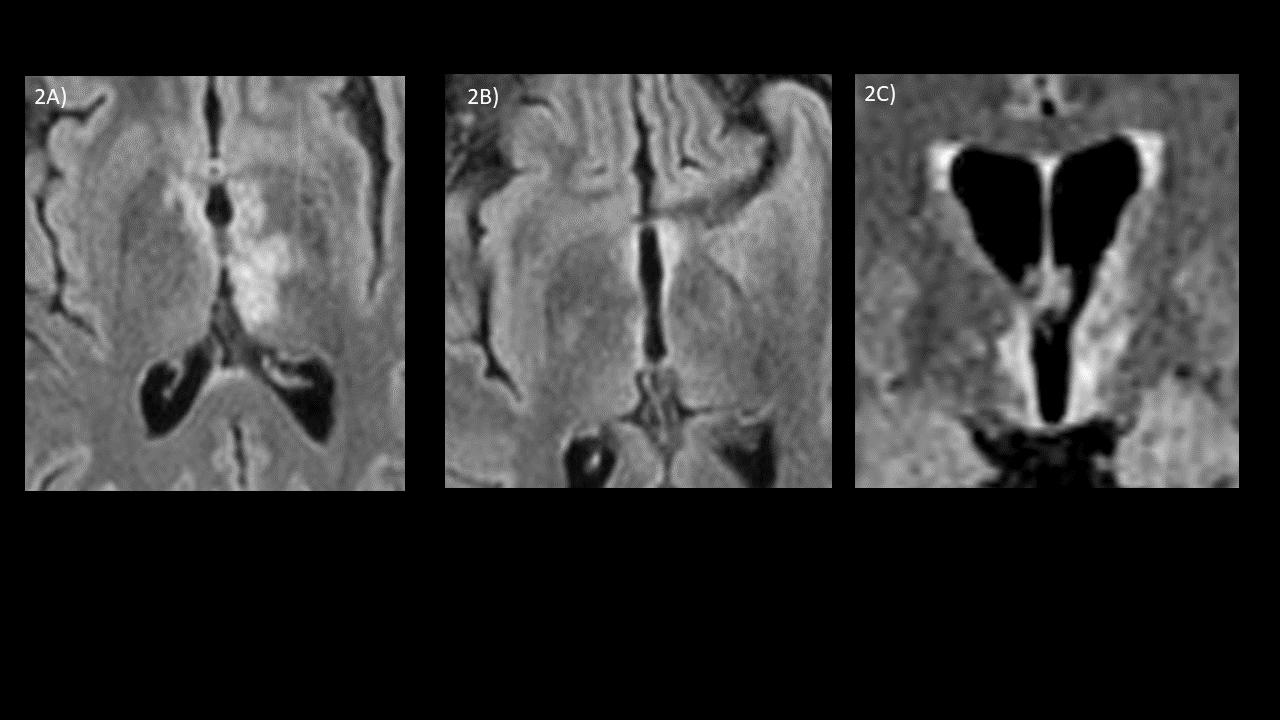

1A) Corte coronal en ponderación T1  y saturación de la grasa tras inyección de contraste demostrando un realce de los nervios ópticos retrobulbares  extendiéndose al la grasa orbitaria adyacente, evocando una neuritis óptica bilateral.

1B) Corte sagital T2  centrado  sobre  la parte distal medular donde se observa una lesión  hiperintensa interesando el cono medular , con  una  longitud  de menos de dos cuerpos vertebrales, evocando una mielitis.

1C) Corte axial centrado sobre la lesión cervical mostrando que ésta ocupa la parte central y posterior derecha  y más del 50% de la sección transversal del cordón medular.

– nervio óptico: pacientes con AQP4-IgG-positivo suelen presentar una afectación bilateral y posterior del nervio óptico con extensión al quiasma. Pacientes positivos para MOG-IgG por lo general exhiben afectación también bilateral pero más anterior y generalmente con realce perineural

– médula espinal: pacientes positivos a AQP4-IgG suelen presentar lesiones extensas en la región cervicotorácica. Sin embargo, el compromiso del cono medular y la médula toracolumbar se asocia a los pacientes con MOG-IgG. En los cortes axiales ambos presentan una localización central y periférica de más de 50 % de la sección medular.